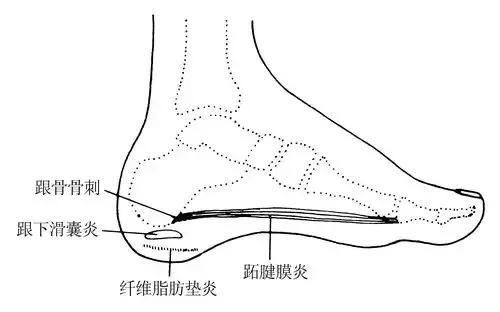

3,跟垫病变

跟垫就是跟骨下面的纤维脂肪垫。

这个纤维脂肪垫平时就像是个脚后跟的小鞋垫一样,在我们每一次走路、跑跳过程中起到吸收震荡,减震缓冲等作用。但是随着年龄的增加,积劳成疾,这个小垫子的内部结构损坏了。这个也很好理解,你就是买的再好的鞋垫子,用的时间久了都会穿烂吧,尤其前脚掌和脚后跟下面的鞋垫最先磨烂。这个脂肪垫也一样,被磨烂了。这时候就会在脚踩地的时候产生疼痛的症状。

除了骨质疏松和微骨折之外,跟骨骨刺有时候也会引起跟痛症。

这种跟骨骨刺在中老年人群中非常常见,但是你可不要认为你的脚跟疼痛就是这个骨刺引起的。这种骨刺我们称之为牵拉骨刺,看下面的图。

这个跟骨骨刺常见的部位往往是跖底筋膜的起点,恰恰是因为跖底筋膜在运动中反复的牵拉这里的骨骼,大脑命令身体里的钙质在这里沉积,来加强这个点(就好像防止这个筋膜从骨骼里拔出来一样),久而久之,就有了这个骨刺。所以,骨刺也很无辜,也很被动。但是我们看到这个骨刺,就知道,这个人的跖底筋膜是一个反复劳损的筋膜,脚后跟是一个反复劳损的脚后跟,脂肪垫也是一个反复劳损的脂肪垫,所以,这个骨刺提示我们,这个人跟痛症的可能性非常大。即使现在还没出现症状,也很可能在不久的将来出现。